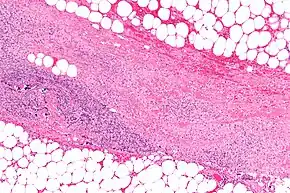

Bacteria

Types of soft-tissue necrotizing infection can be divided into four classes according to the types of bacteria infecting the soft tissue. This classification system was first described by Giuliano and his colleagues in 1977.[4][2]

Type I infection: This is the most common type of infection, and accounts for 70 to 80% of cases. It is caused by a mixture of bacterial types, usually in abdominal or groin areas.[4] This type of infection is usually caused by various species of Gram-positive cocci, (Staphylococcus aureus, Streptococcus pyogenes, and enterococci), Gram-negative rods, (Escherichia coli, Pseudomonas aeruginosa), and anaerobes, (Bacteroides and Clostridium species).[4] Populations of those affected are typically older with medical comorbidities such as diabetes mellitus, obesity, and immunodeficiency.[4] Usually, trauma is not the cause of such infections. Previous history of abscess infection or gut perforation with bacterial translocation may be elicited. Clostridial infection accounts for 10% of type I infection. Clostridium species involved are Clostridium perfringens, Clostridium septicum, and Clostridium sordellii, which typically cause gas gangrene (also known as myonecrosis). Clostridium perfringens produces two deadly toxins: alpha-toxin and theta-toxin. Alpha-toxin causes excessive platelet aggregation which blocks blood vessels and deprives the vital organs of oxygen supply. This creates an acidic, oxygen-deficient environment for the proliferation of bacteria. When alpha-toxin is absorbed by soft tissues, it can inhibit the migration of white blood cells from blood vessels into the soft tissue, thus impairing phagocyte function. The two toxins together can cause destruction of red blood cells in blood vessels, damage to the integrity of the blood vessels, and suppression of heart function.